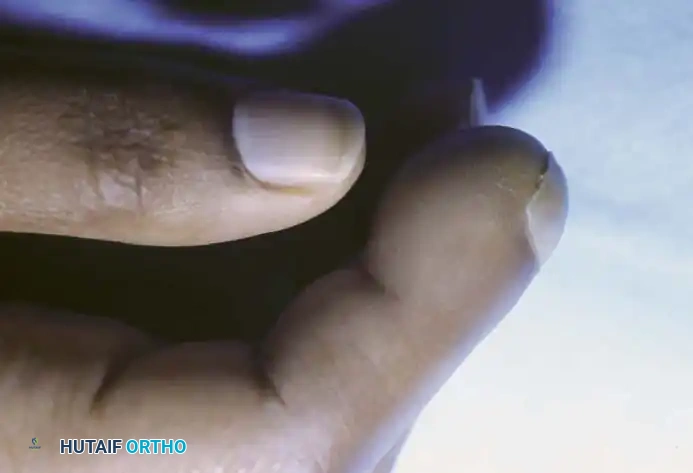

Clinically, the patient develops a hard, rubbery, non-tender subcutaneous mass. The distal phalanx is the most common osseous site, where the expanding cyst can cause pressure erosion of the bone.

Clinical appearance of an epidermoid inclusion cyst on the index finger following a remote puncture wound.